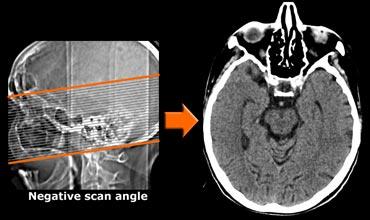

Giao thức chụp CT

CT có thể hữu ích khi có chống chỉ định với MRI hoặc khi mục đích duy nhất của chẩn đoán hình ảnh là loại trừ các nguyên nhân gây suy giảm nhận thức có thể điều trị bằng phẫu thuật.

Trên mặt phẳng ngang, góc quét cần song song với trục dài của thùy thái dương.

Sử dụng CT đa dãy đầu thu sẽ cho phép tái tạo các hình ảnh theo mặt phẳng coronal vuông góc với trục dài của thùy thái dương để hiển thị tối ưu hồi hải mã.